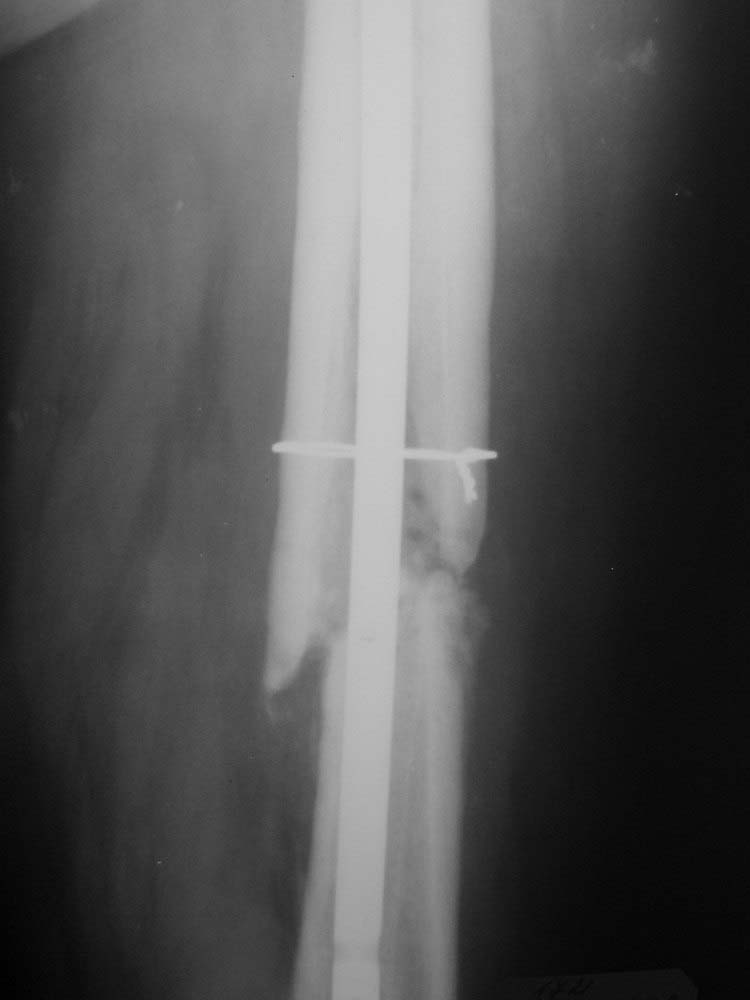

Пациент (мужчина), 34 года. Травма в результате ДТП в апреле 2011 года. Проводилось оперативное лечение – закрытая репозиция, остеосинтез AFN. В октябре 2011 года – декортикация, тунелизация, фиксация отломков верхней трети диафиза бедренной кости проволочным серкляжом, удаление дистального блокирующего винта. На контрольных рентгенограммах определяется миграция шеечных винтов конструкции. Пациент передвигается на костылях с дозированной нагрузкой на ногу (полная нагрузка болезненна в области тазобедренного сустава). Вариант лечения - тотальное эндопротезирование тазобедренного сустава+остеосинтез верхней трети диафиза бедренной кости (ретроградным стержнем ЦИТО, пластиной, АНФ).Жду Ваших комментариев